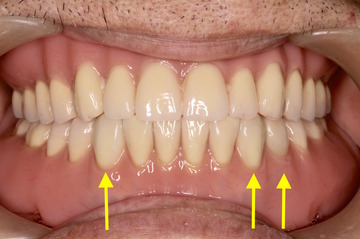

ケース NO.2 ⬆︎ 残した歯 ⬆︎ 抜いた歯

上がレジリエンツテレスコープ義歯、下が総入れ歯

この患者様は下アゴが分からない程痩せてしまっているため、

高度な技術が必要となります。